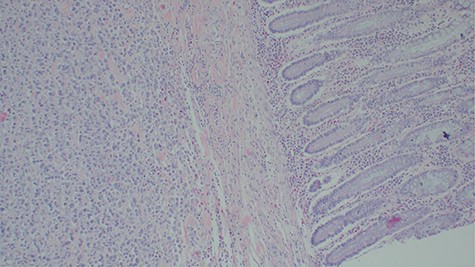

After a tumor board discussion, a radical cystectomy (Fig. 4) with MAINZ II urinary diversion was performed upon obtaining the patient’s written informed consent. Intraoperative findings were a bladder mass with limited mobility and part of the sigmoid colon ~4 cm was adhered to the mass. Resection of part of the sigmoid colon and end-to-end anastomosis were done. Homeostasis was achieved and abdomen was closed in layers. A pathologic stage of pT4N0M1 was given. Postoperative treatment included intravenous 100 mg of pethidine after every 8 hours for 24 hours, 500 mg of metronidazole three times a day for 5 days, 1 g of ceftriaxone once a day for 5 days and rectal tube for 7 days. The histological findings of the tumor in the radical cystectomy specimen were similar to that in the incisional biopsy with colonic metastasis (Fig. 5). On the 10th day after operation, the patient could pass urine and stool well, and his condition was fairly improving. He was referred to the oncology department for chemotherapy. Unfortunately, the patient developed and died of sepsis before the initiation of oncological treatment.

Histopathology of the urinary bladder osteosarcoma metastasizing into the colon. Adjacent normal colon mucosa is seen near the tumor (H&E ×200).